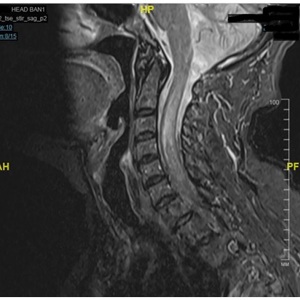

Восстановление ходьбы после операции удаления опухоли шейного отдела спинного...

В данной статье представлен клинический случай благоприятного восстановления пациентки после оперативного лечения интрамедуллярной опухоли на уровне С4-Th1...